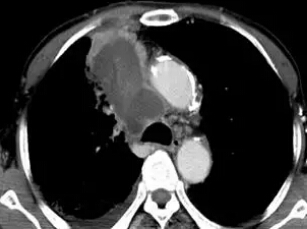

上圖是術(shù)后第三天CT增強(qiáng)掃描的圖片,雖然病灶的部位非常不好,靠近大血管、氣道,但可以看到腫瘤內(nèi)部絕大部分都被一次消融殺死,患者本人和遠(yuǎn)道趕來(lái)的家屬都非常滿意這個(gè)結(jié)果。